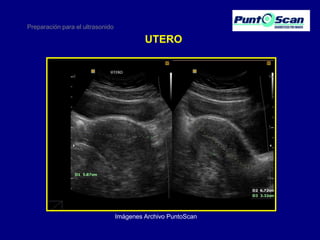

UTERO

Imágenes Archivo PuntoScan

Preparación para elultrasonido UTERO Imágenes Archivo PuntoScan

• 27.